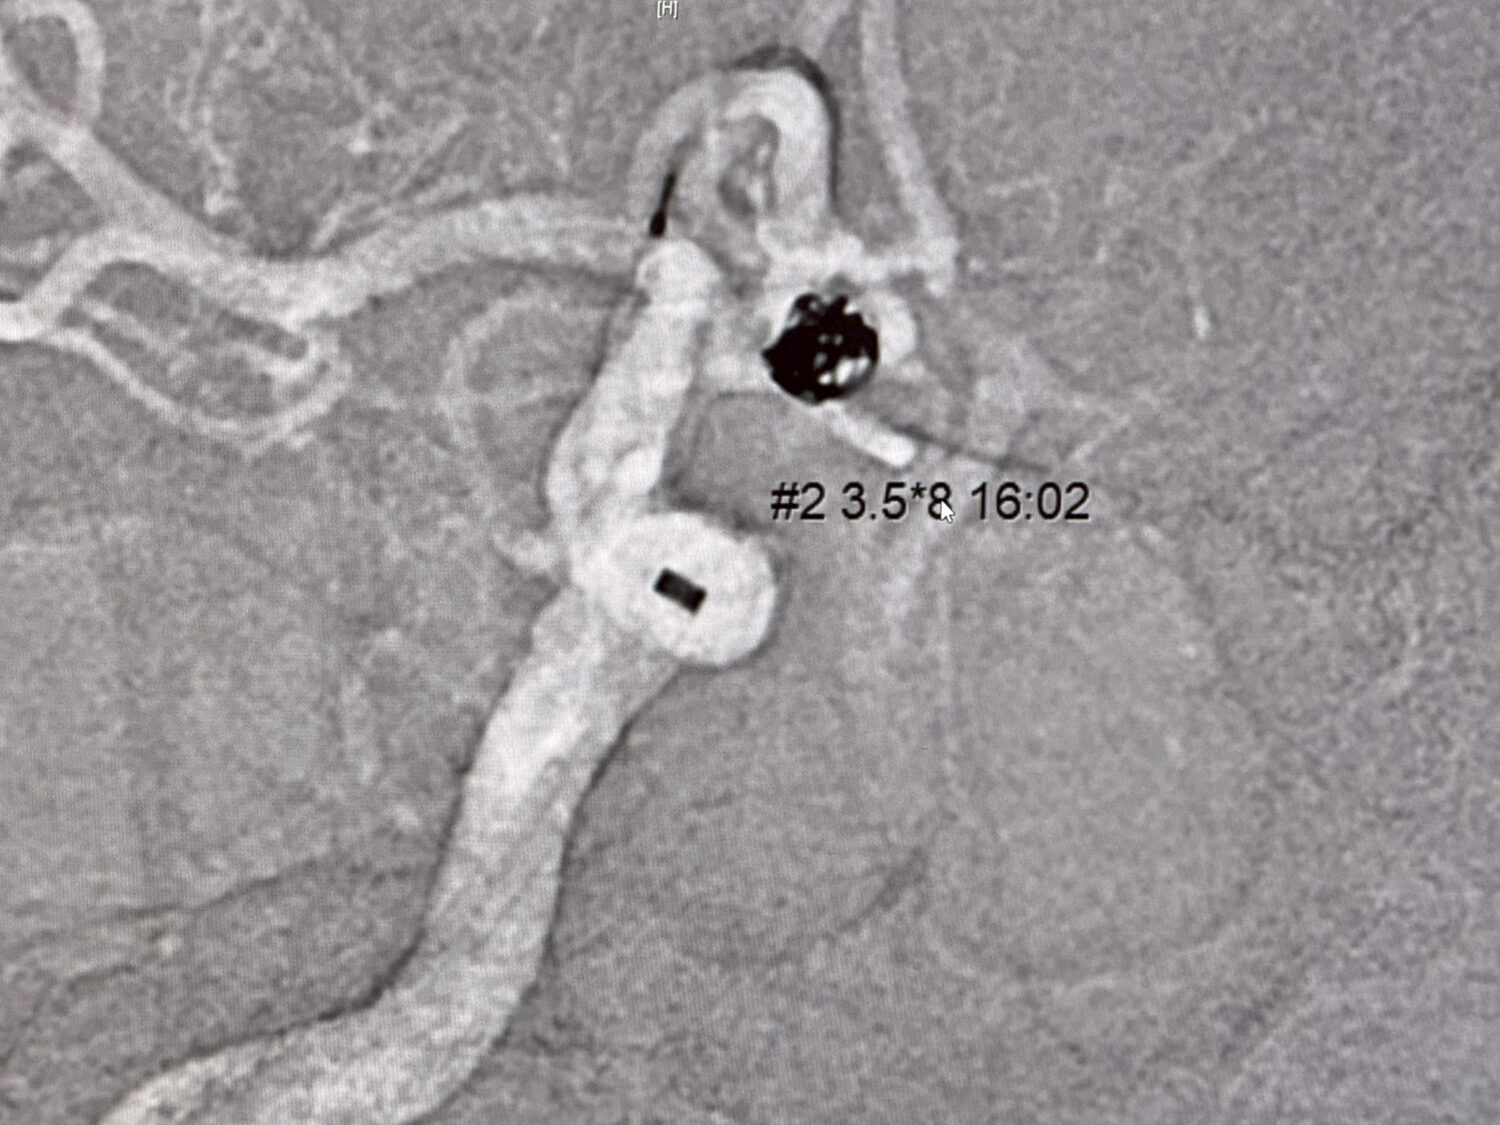

【警政時報 張家燁/新竹報導】新竹一名68歲王姓婦人清晨被家人發現昏倒浴室門口,緊急送醫後啟動「急性腦中風區域聯防」機制轉送東元綜合醫院,經電腦斷層檢查,神經內科蔡坤璋醫師診斷為蜘蛛網膜下腔出血,進一步血管攝影發現前大腦交通動脈處有一顆約5.5×5.5公厘動脈瘤破裂出血,病況危急。

醫療團隊立即進行「動脈瘤栓塞術」,透過導管從股動脈進入腦血管,使用柔軟線圈填塞破裂的動脈瘤,精細操作成功止血,避免二度破裂危機,婦人術後病情穩定,平安出院並持續回診復健,成功逃過一劫。